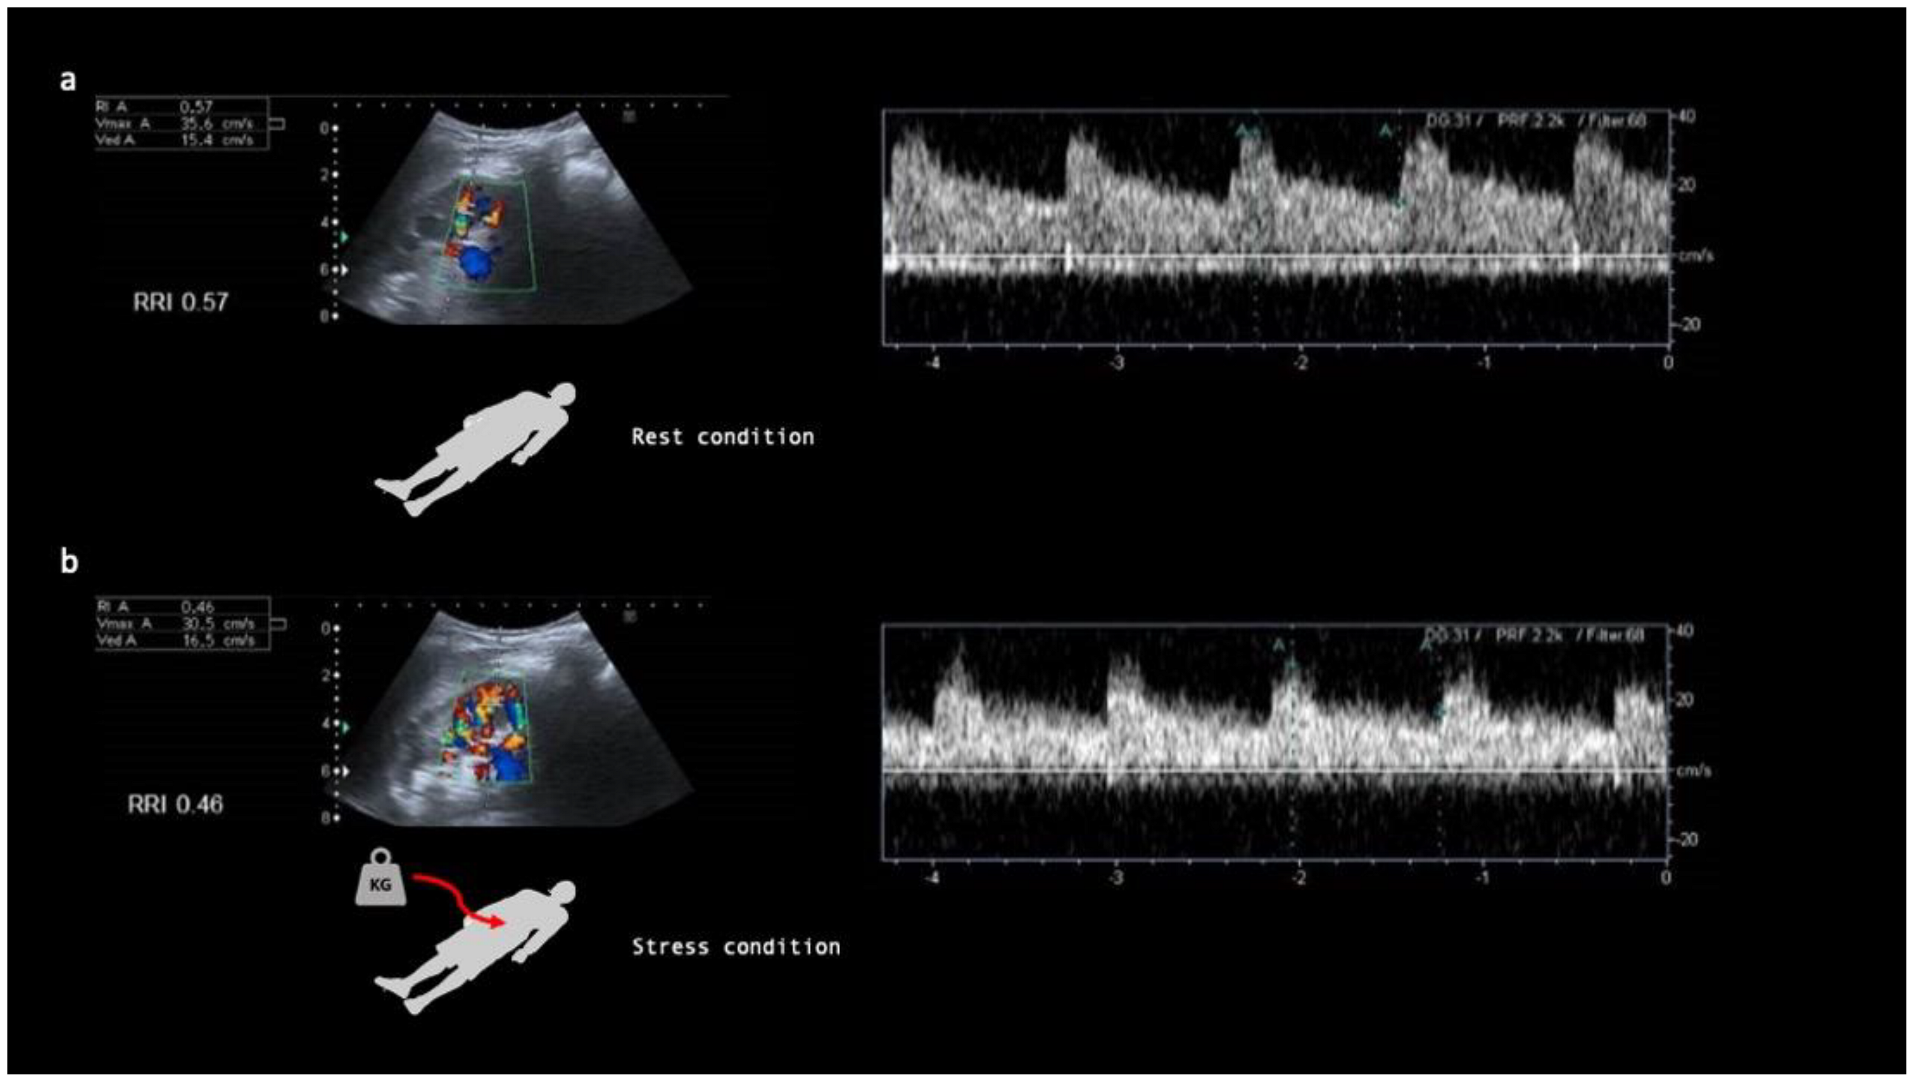

2.2. Baseline RRI Measurement

2.3. Renal Stress Test (RST)

- Samoni, S.; Nalesso, F.; Meola, M.; Villa, G.; De Cal, M.; De Rosa, S.; Petrucci, I.; Brendolan, A.; Rosner, M.H.; Ronco, C. Intra-Parenchymal Renal Resistive Index Variation (IRRIV) Describes Renal Functional Reserve (RFR): Pilot Study in Healthy Volunteers. Front. Physiol. 2016, 7, 286. [Google Scholar] [CrossRef]

- Samoni, S.; Villa, G.; De Rosa, S.; Husain-Syed, F.; Guglielmetti, G.; Tofani, L.; De Cal, M.; Nalesso, F.; Meola, M.; Ronco, C. Ultrasonographic Intraparenchymal Renal Resistive Index Variation for Assessing Renal Functional Reserve in Patients Scheduled for Cardiac Surgery: A Pilot Study. Blood Purif. 2022, 51, 147–154. [Google Scholar] [CrossRef]